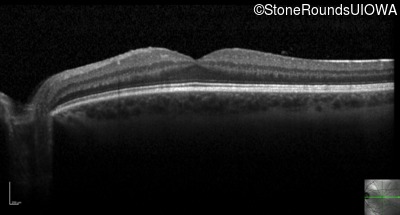

Optical Coherence Tomography - Right - 20/15 -1 sc

Exemplar / OCT Stack

OCT Stack

Optical Coherence Tomography - Left - 20/20 -1 sc